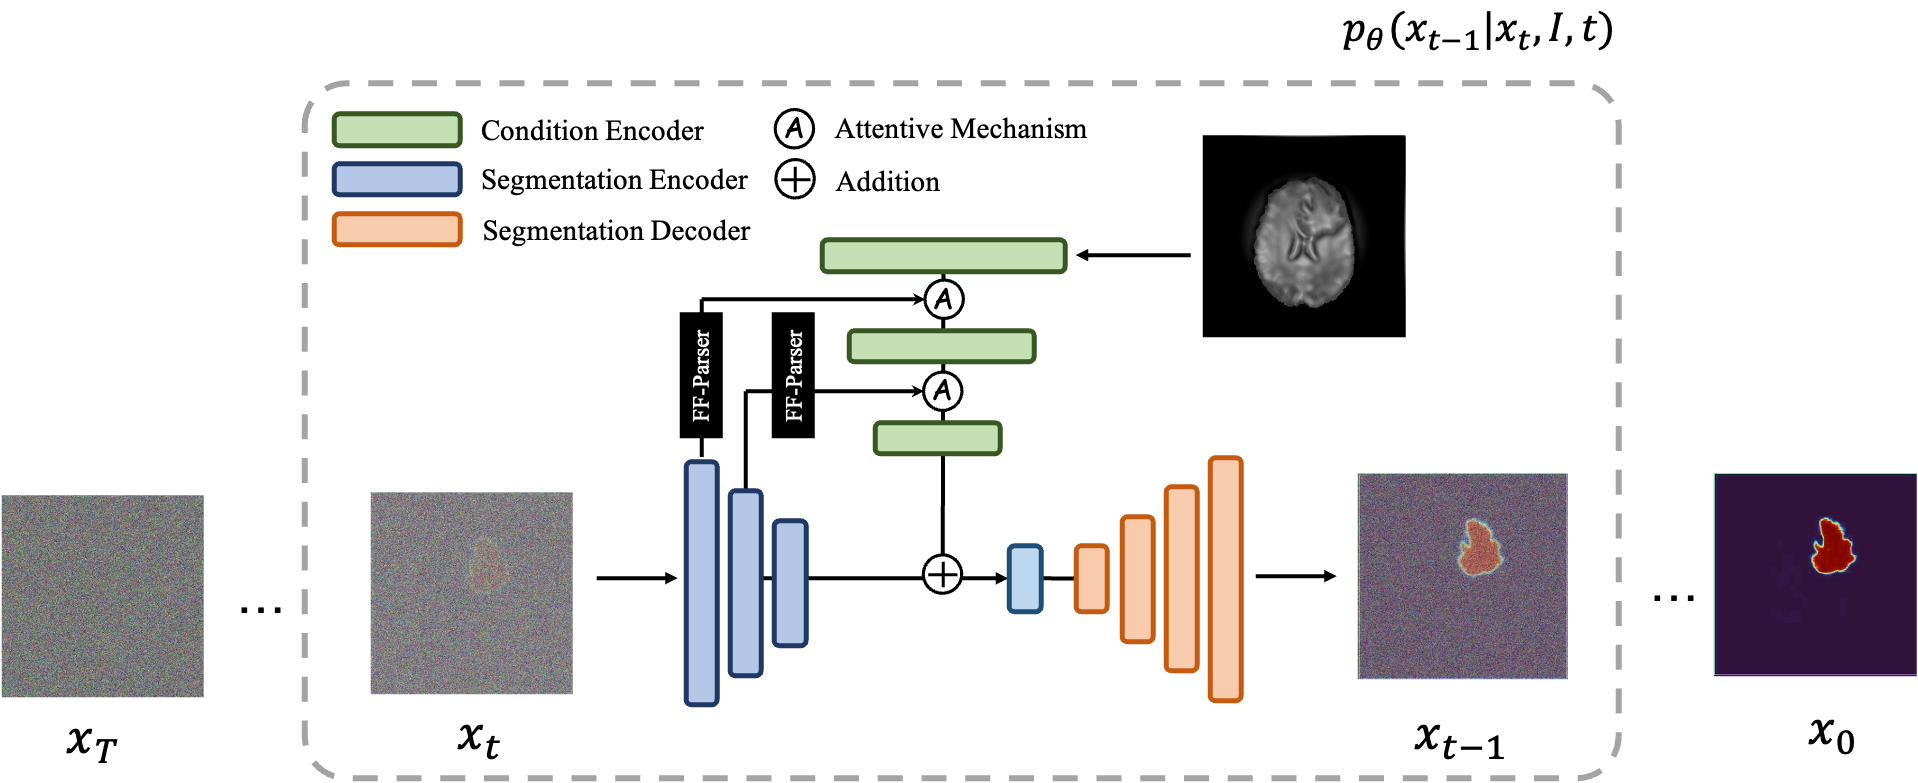

In the course of building my personal medical image segmentation toolkit capabilities to study ISLES24, I've been working on expanding into Diffusion models. Specifically, the MedSegDiff model.

The implementation itself was for me as an absolute beginner in the field of diffusing anything, quite overwhelming. It is now that after a bit around the block that I have come to understand the repo as standing on the shoulders of the giant

I found various issues with the repo that I elected to begin with a base implementation from https://github.com/deepmancer/medseg-diffusion

This was an juypter notebook that I broke down into components classes and files, and started adding experimental structures that would allow me to conduct configurable, extensible research into using this model for the ISLES24 Dataset as well as ported over my ISLES24 manipulation code from my existing SwinUNetR experiments.

https://github.com/openai/guided-diffusion/ and https://github.com/openai/improved-diffusion. In hindsight, now that I'm writing up this post, I've come to immediately recognize how the official MedSegDiff repo builds in the code structure left by the guided diffusion repo, adding dataset loaders, a new model structure and relevant changes to get these to click, but otherwise, this was the same repo.